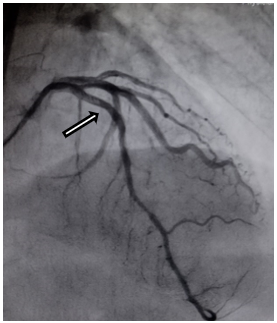

Subsequent coronary angiography showed 20% recanalisation of the proximal LAD obstruction (Figure. 3a, marked with arrow head). One drug-eluting stent (3.0 x 20.0 mm) was implanted across the lesion without complications (Figure. 3b, marked with arrow head). He was mobilized and discharged home in a stable condition. Echocardiogram at follow up two weeks later shows improvement of LVEF (50.6%).

Figure 3 (b): Patient’s Coronary Angiogram after stenting.